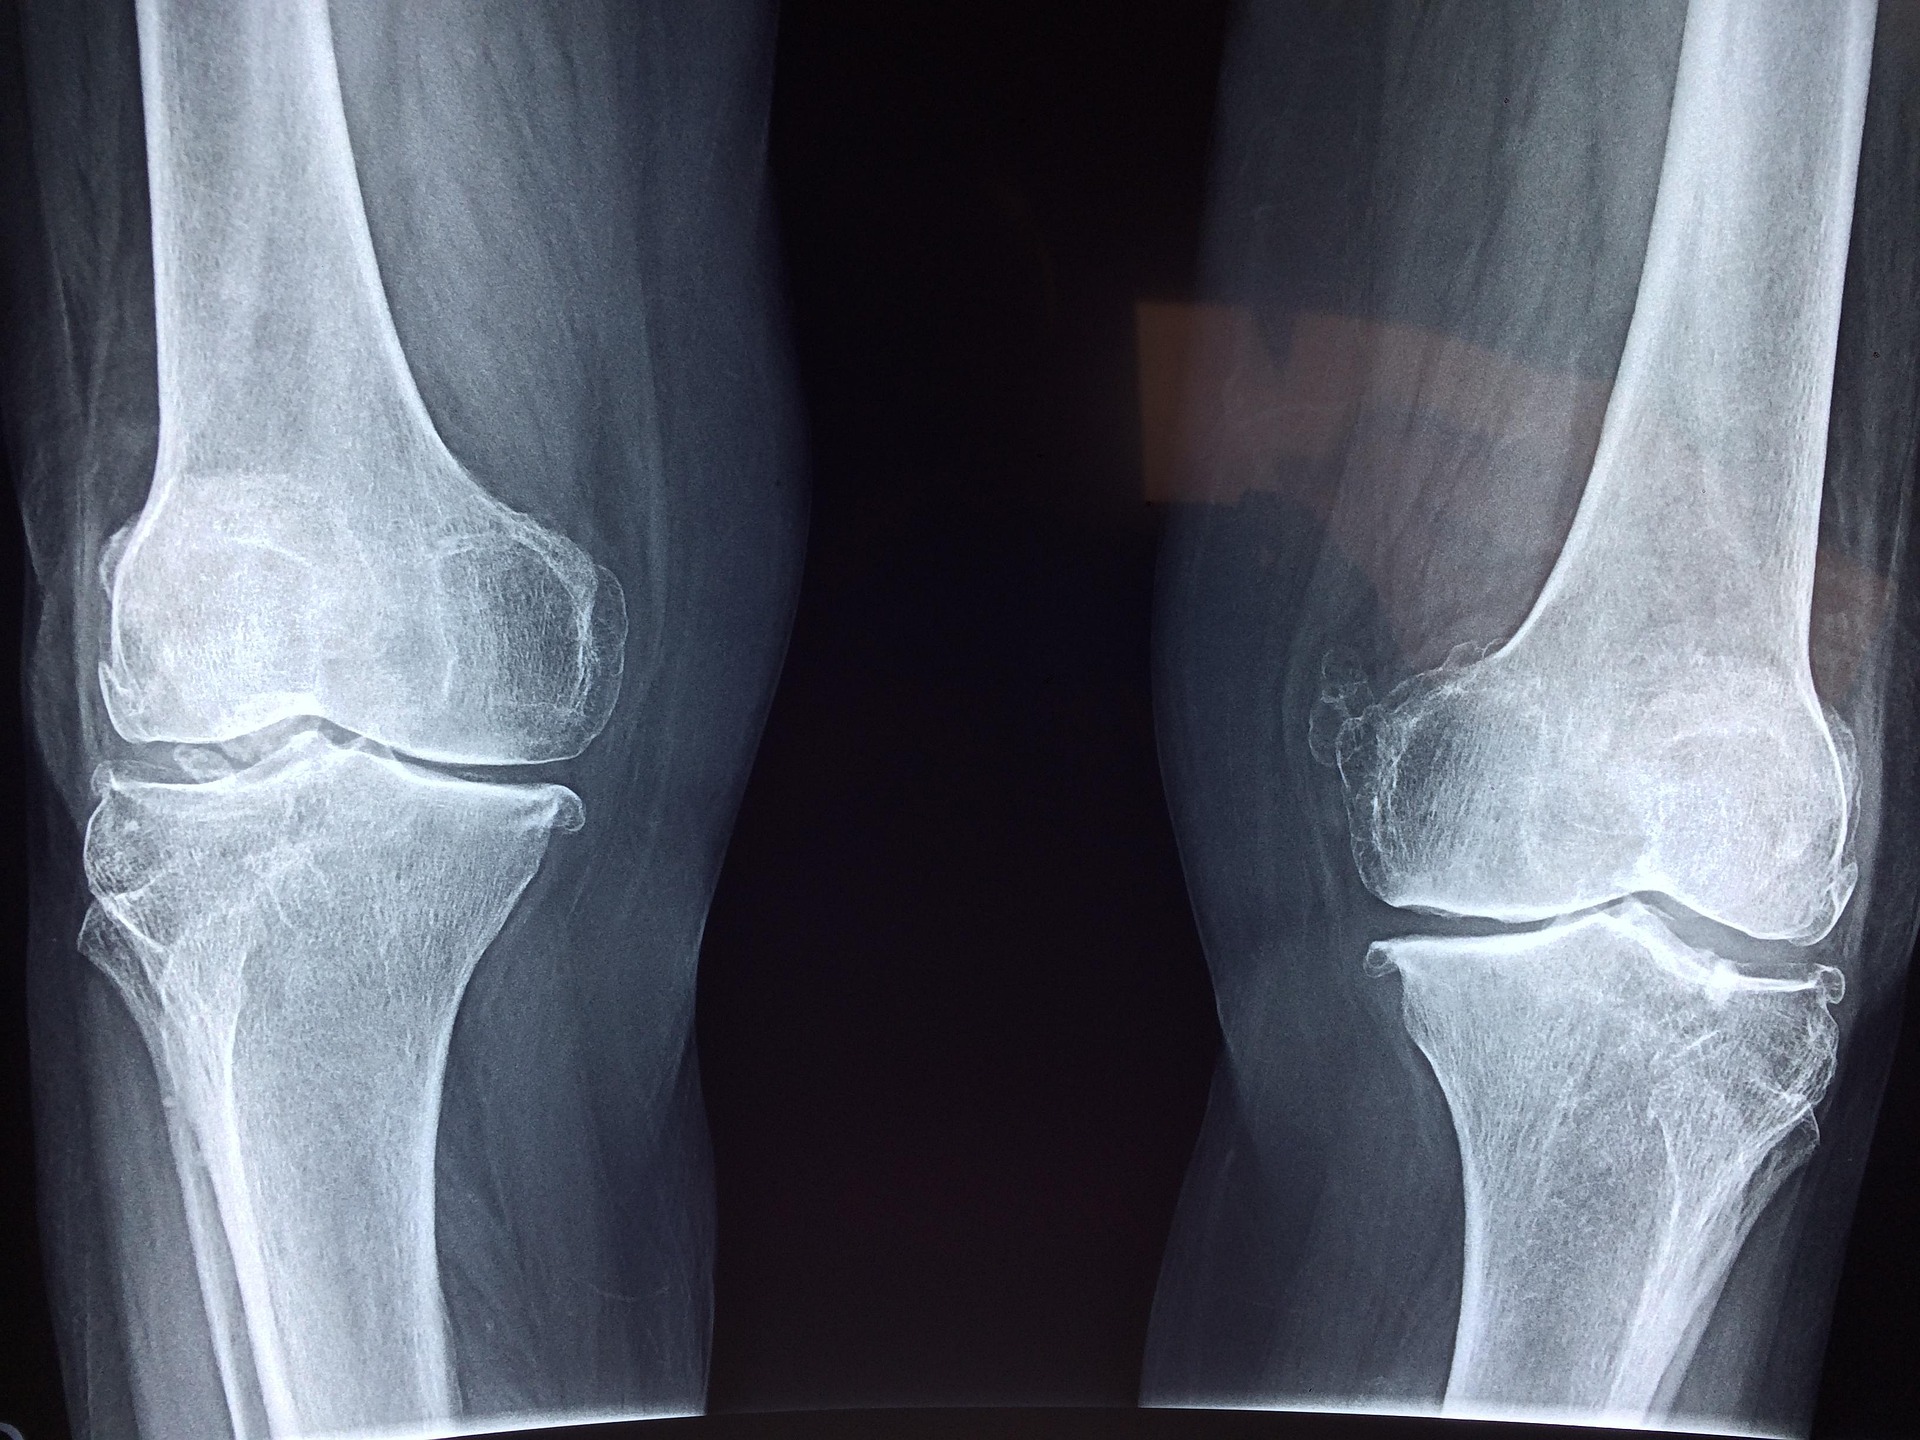

특히 무릎이나 고관절처럼 체중을 지탱하는 관절은 작은 충격에도 누적 손상이 생길 수 있다.